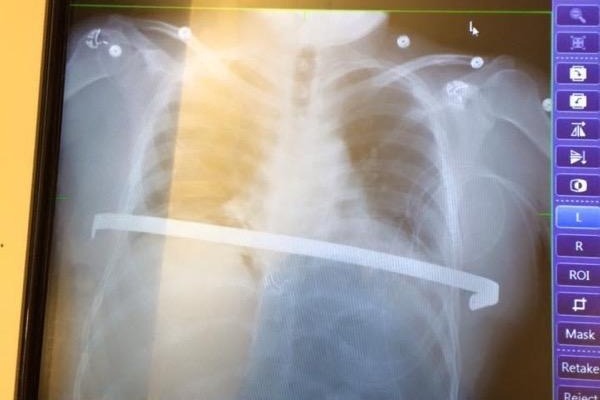

Josh was born with a condition known as pectus excavatum. It is a condition in which a person's breastbone is sunken into one's chest. Severe cases of pectus excavatum can eventually interfere with the function of the heart and lungs. Josh's case was so severe that three years ago it was determined he needed what is called a Nuss Procedure, whereby one to three curved metal bars are inserted behind the sternum in order to push it into a normal position. In this surgery they make a tunnel under your rib cage and over your lungs and heart so that a pre-bent bar can be inserted flat, attached to the side of the ribs, and cranked up to micro fracture all of the ribs and sternum, while at the same time supporting the rib cage so that it is able to heal in the correct form to allow the heart and lungs to function properly. The bars are then left in for a period of three years at which time they need removed. As you can imagine it is an extremely painful process, and despite many setbacks since having it done, Josh has not given up and continues to fight. The procedure Josh currently needs done is to have those bars removed. The total cost is approximately $17,000 and he has an immediate deductible to pay for $2000.00 in order to proceed. Thank you in advance for any contribution you may wish to offer and God bless. You are much appreciated.